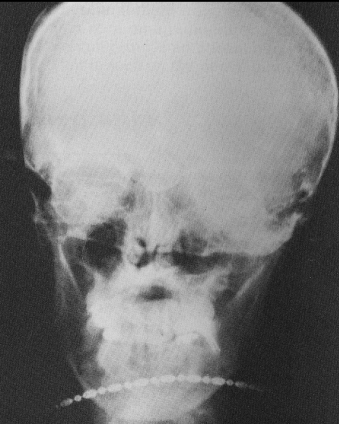

Glasses on PAN

Daisy chain

hearing aid